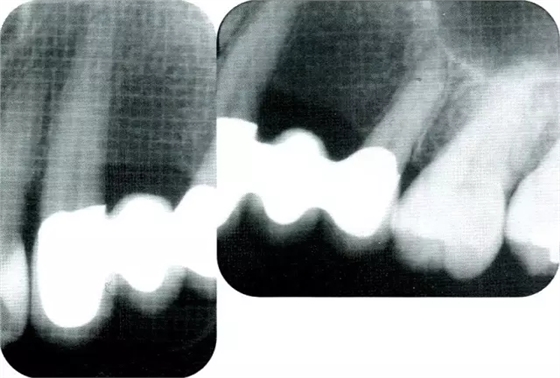

▲圖8-2初診時(shí)的x片。尖牙遠(yuǎn)中確認(rèn)有垂直性骨缺損。

▲圖8-9最終修復(fù)體戴上時(shí)的x片,可確認(rèn)尖牙近遠(yuǎn)中部的牙槽骨高度相同。

▲圖8-10術(shù)后11年的x片。術(shù)后的骨水平得到了維持。